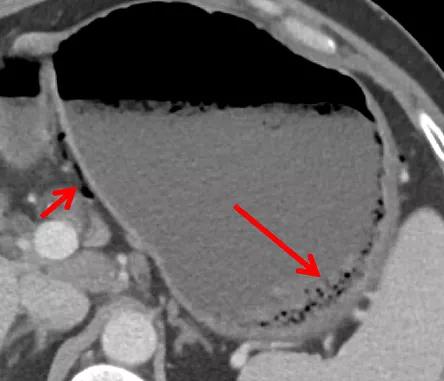

中年男性,既往肝硬化,头晕就诊。CT 增强动脉期示胃腔内异常高密度,代表血肿。胃壁上见多发迂曲的小血管。